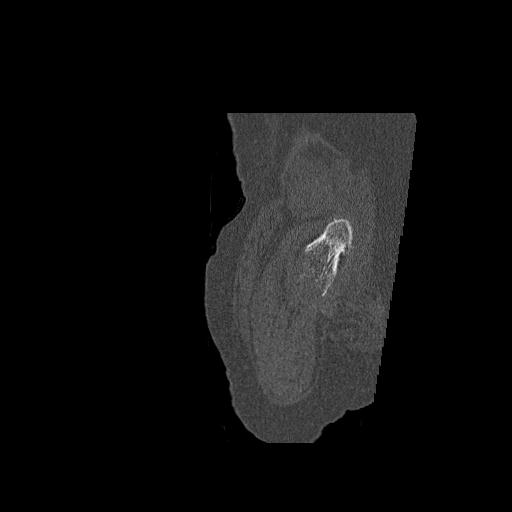

49554 3/13 膝 4R 3/16 4R 1/18 2R 78歳男性 膝蓋骨骨折